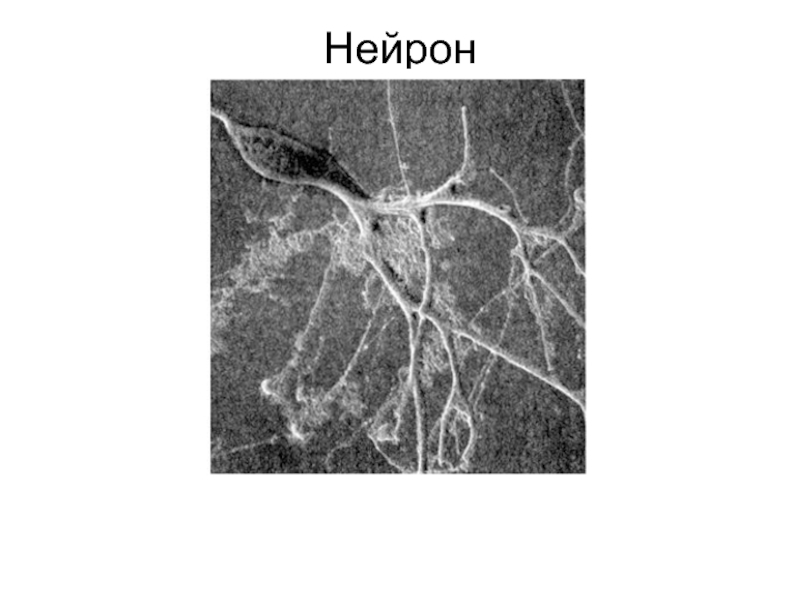

Мир нейроцитов: исследование нервных клеток